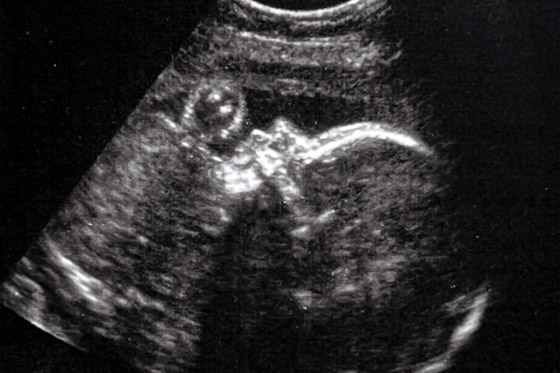

في حين أُجرِيَت العملية على جنينٍ عمره 34 أسبوعاً من الحمل؛ حيث أُدخِلَت إبرة في رحم والدته. واستُخدِمَت صور الموجات فوق الصوتية لتوجيهها عبر مؤخرة رأس الجنين. ثم استُخدِمَت الإبرة لوضع قسطرة في الوعاء الدموي المُوصِل غير الطبيعي، وإدخال لفافة معدنية خاصة لتقليل عرض الوعاء الدموي؛ وبالتالي إبطاء تدفق الدم. واستغرقت العملية أقل من ساعتين، وكانت الأم والجنين تحت التخدير. ووُلِدَت الطفلة قبل أوانها، بعد العملية بيومين.